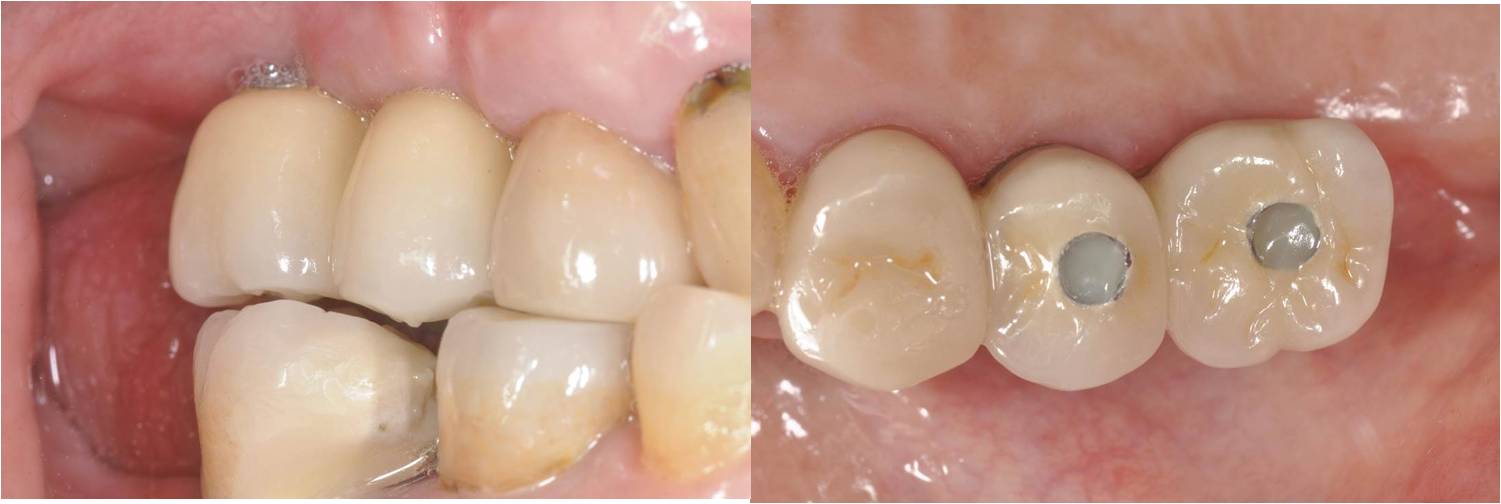

口內螺絲固定

術前、術後比較